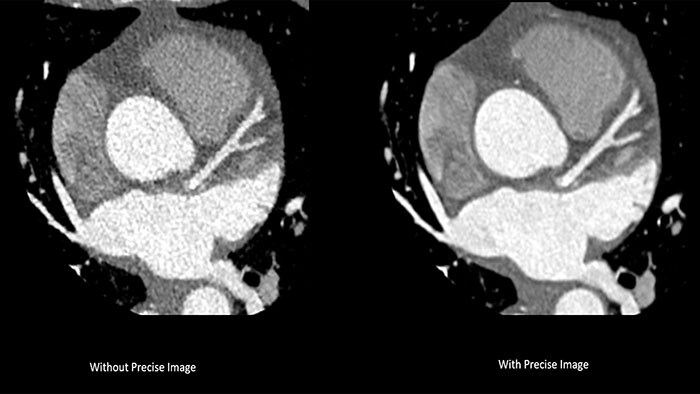

De nieuwe CT 5300 is al in verschillende Europese ziekenhuizen geplaatst. "CT 5300 biedt CT-beeldvorming van top tot teen, gecombineerd met hoogwaardige functionaliteit zoals coronaire angiografie, waardoor een extreem breed spectrum aan toepassingen wordt geboden en we een grotere hoeveelheid patiënten beter kunnen beheren", aldus Dr. Hilmar Kühl, hoofd Radiologie in het St. Bernhard-ziekenhuis Kamp-Lintfort, Duitsland. "Met dit nieuwste systeem van Philips zien we een verbetering in de beeldkwaliteit met Precise Imaging, en voor het eerst kunnen we nu de cardiale anatomie visualiseren door Precise Cardiac vrijwel artefactvrij te gebruiken, wat zeer waardevol is om de cardiale zorg te helpen verbeteren voor onze patiënten."

De nieuwe scanner heeft Nanopanel Precise, dat speciaal voor op AI gebaseerde reconstructie vanaf de basis is opgebouwd. Deze gloednieuwe detector maakt gebruik van de volledige mogelijkheden van Philips Precise Image-reconstructiesoftware om beelden van hoge kwaliteit te bieden bij een veel lagere stralingsdosis. Bij een 80% lagere dosis behaalt Precise Image tot 85% minder ruis en 60% betere detecteerbaarheid bij laag contrast dan conventionele beeldreconstructie [2]. In combinatie met Precise Cardiac-bewegingscompensatie maakt Precise Image de CT 5300 bijzonder geschikt voor hoogwaardige, bewegingsvrije cardiale beeldvorming bij patiënten met een hoge hartslag of hartslagvariabiliteit.